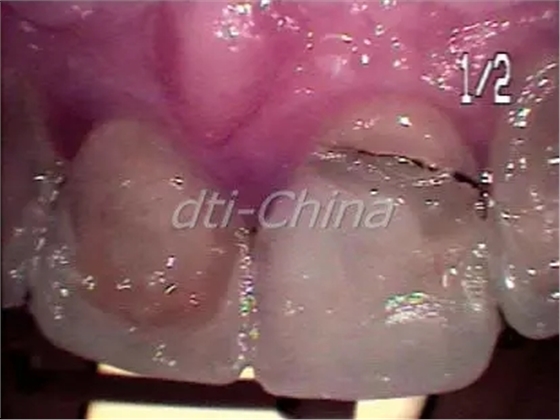

這是一位30多歲的健康男性,在我的診所檢查到右側上頜中切牙折斷,患者幾年前上中切牙和側切牙已經(jīng)使用長石質陶瓷進行了修復,他的這顆前牙有運動創(chuàng)傷的病史,并且做了根管治療。上頜切牙近期的根尖片顯示內吸收(圖5),這名患者右側上頜中切牙因為跌倒持續(xù)創(chuàng)傷導致冠的完全折斷(圖6),這牙齒不能復原。患者對不同治療方案的進行評估后,決定進行即刻種植修復??紤]到在美學區(qū)相鄰種植體植入會導致牙齦組織結構不良,盡管左側上頜側切牙也顯示內吸收,但患者還是決定稍后再處理這顆牙。牙周醫(yī)生對于右側上頜中切牙的即刻種植手術進行了評估,這名患者的治療跟第一個病例的患者相同。右側中切牙被拔除,Nobel Replace Tapered Groovy (內連接) 5.0 mm x 13 mm植體植入,利用一個凍干脫鈣骨移植物和一個膠原膜對手術位點進行骨移植增量。愈合基臺維持基本輪廓,患者即刻獲得一個非功能性的臨時冠。